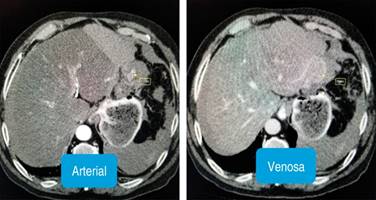

Figura 2: Tomografía axial computarizada simple y contrastada de abdomen y pelvis, corte axial. Se observa el tumor hepático en segmento II, se observa la captación de contraste en fase arterial y lavado en la fase venosa (wash out).